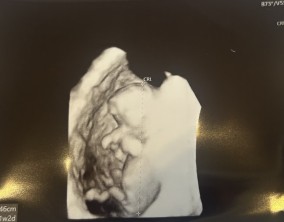

심장소리 이후, 함께 웃게 된 임밍아웃

유정원장님 치료 과정 내내 항상 따뜻하게 진료해 주셔서 감사한 마음이 큽니다. 덕분에 불안한 순간에도 마음을 다잡고 치료를 이어갈 수 있었습니다.